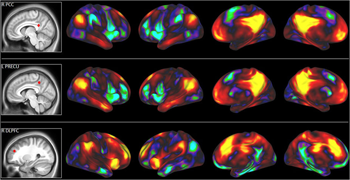

In a study published earlier this year, he and his team studied 71 adults. The researchers tested the volunteers’ fluid intelligence with a standard IQ test that had been designed for adults. At the same time, they mapped out which areas of test takers’ brains were working hardest. They did this using a brain scan called magnetic resonance spectroscopy, or MRS. It uses magnets to hunt for particular molecules of interest in the brain.

As brain cells work, they gobble up glucose, a simple sugar, and spit out the leftovers. MRS scans let researchers spy those leftovers. That told them which specific areas of people’s brains were working hard and breaking down more glucose.

People who scored higher on fluid intelligence tended to have more glucose leftovers in certain parts of their brains. These areas are on the left side of the brain and toward the front. They’re involved with planning movements, with spatial visualization and with reasoning. All are key aspects of problem solving.